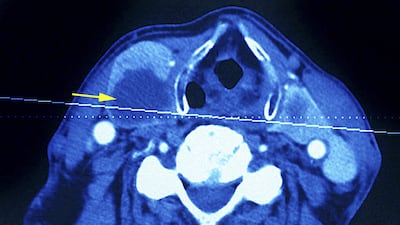

My white blood cells were high and my thyroid function was outside the normal range. A later ultrasound found a suspicious nodule in my thyroid gland and Hashimoto’s disease. A second ultrasound and biopsy found papillary carcinoma, the most common type of thyroid cancer.